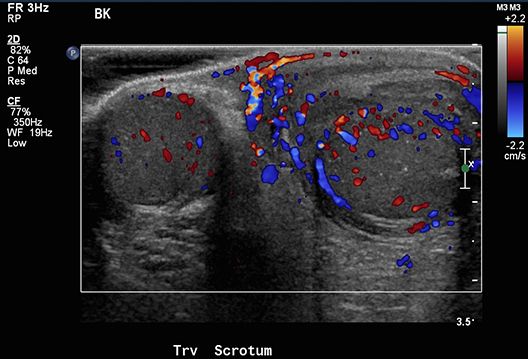

Long-time proponent of ultrasound for breast screening, Kevin M. Kelly, MD, discusses what radiologists need to know.

Screening ultrasounds plus mammography may find more cancers in women who have breast dense tissue.